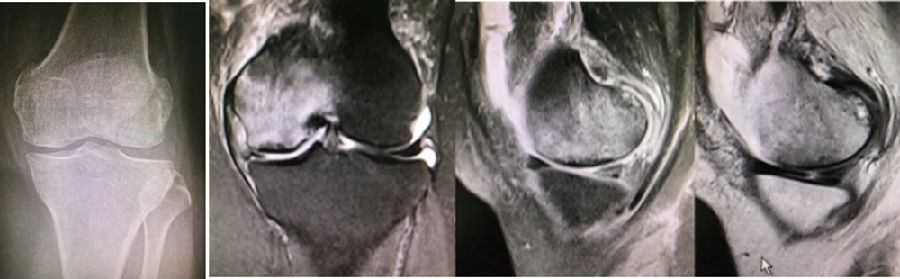

病例:女,65岁,主诉左膝关节内侧疼痛2月余。2017年11月X光未见左膝骨质异常。MR见股骨内侧髁骨坏死,半月板相对突出百分比(RPE)28.3%,合并内侧半月板后根部撕裂,矢状位病变区域前后径为11.67mm,关节线会聚角2.68°

予消炎止痛药物口服、静滴唑来膦酸钠注射液,避免负重6周,后改部分负重,12周后全负重。

2018年2月复查MR见骨髓水肿明显吸收,坏死灶边界清晰,半月板相对突出百分比(RPE)28.92%

2018年6月复查MR见骨髓水肿基本完全吸收,坏死区修复良好,半月板相对突出百分比(RPE)38.54%,患者临床症状消失。

提示坏死好转了,但半月板突出进展了,膝关节的退变加重了。